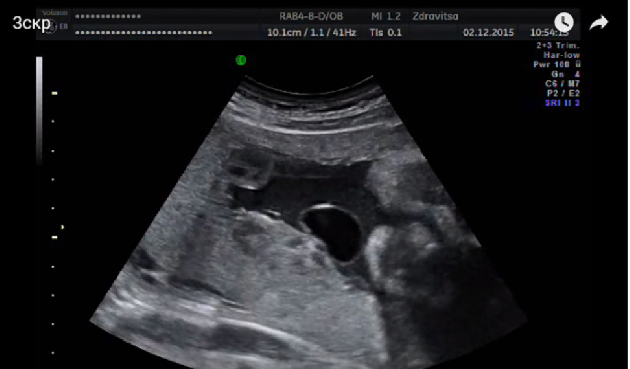

3 скрининг

3/3 Геннадьевич?Впр: двухстворчатый аортальный клапан без стеноза. Омфаломезентериальная киста.

А почки как-то без внимания оставил, киста связана с пуповиной? где?